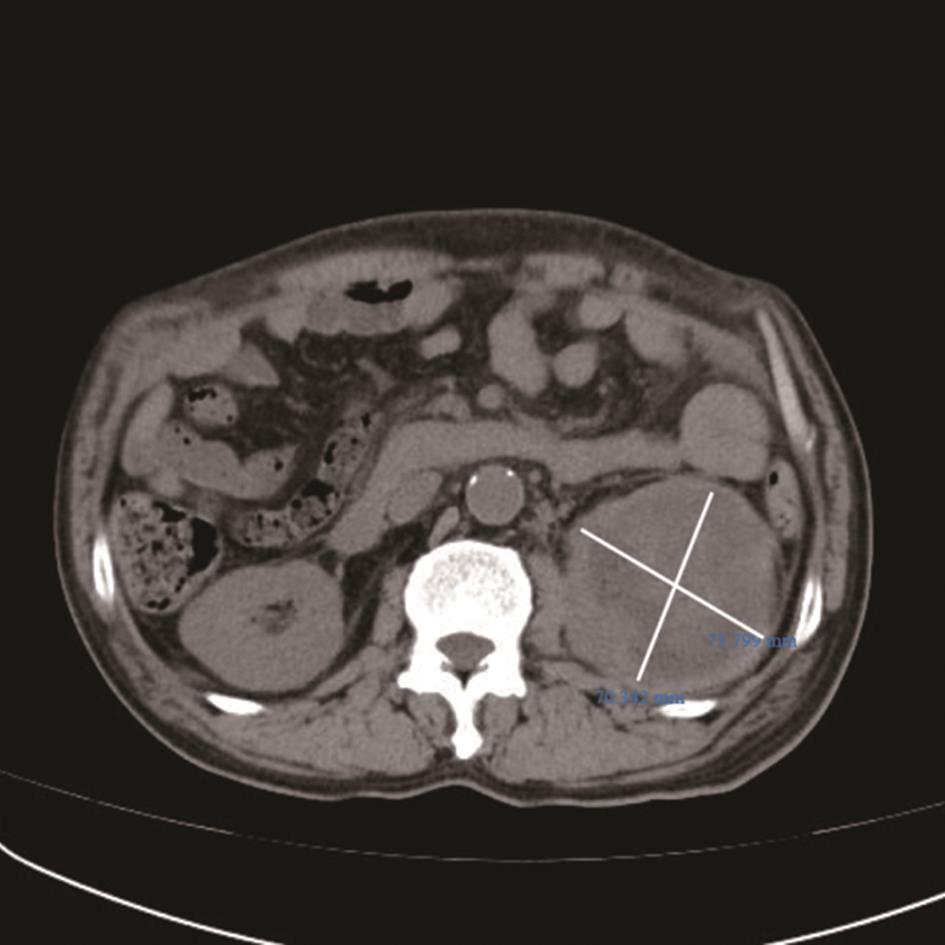

• 转移性上尿路上皮癌在维迪西妥单抗联合替雷利珠单抗新辅助治疗后行根治性肾盂癌切除术1例报道

2023, 48(8):1005-1008. DOI: 10.13406/j.cnki.cyxb.003299

摘要 (52) HTML (36) PDF 2.16 M (1929) 评论 (0) 收藏

摘要: